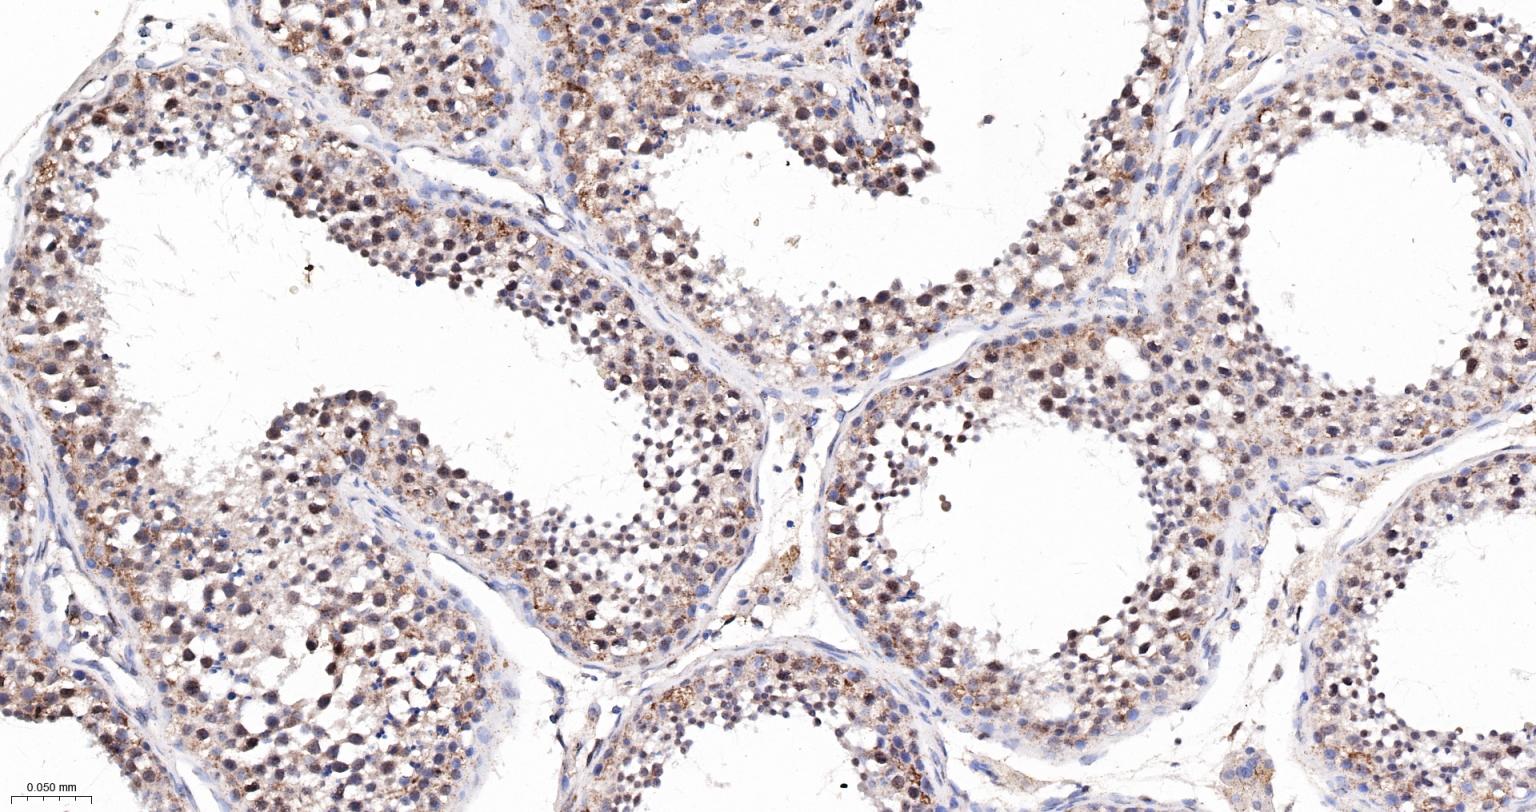

Paraformaldehyde-fixed, paraffin embedded Human Testicles; Antigen retrieval by boiling in sodium citrate buffer (pH6.0) for 15 min; The section was incubated with MAD2L2 Monoclonal Antibody, Unconjugated (bsm-61670R) at 1:200 overnight at 4°C, followed by conjugation to the bs-0295G-HRP and DAB (C-0010) staining.